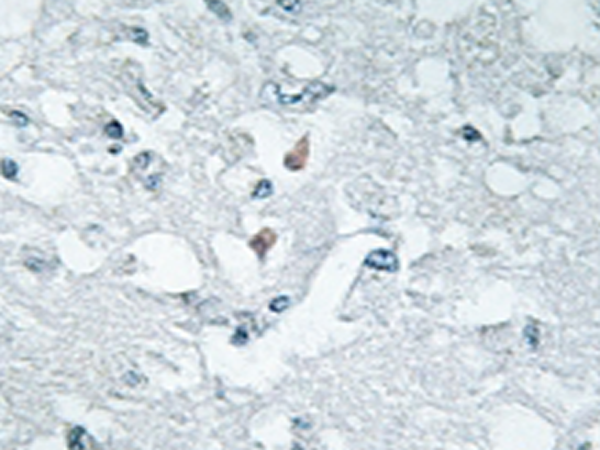

IHC positive control: |

Human brain tissue |